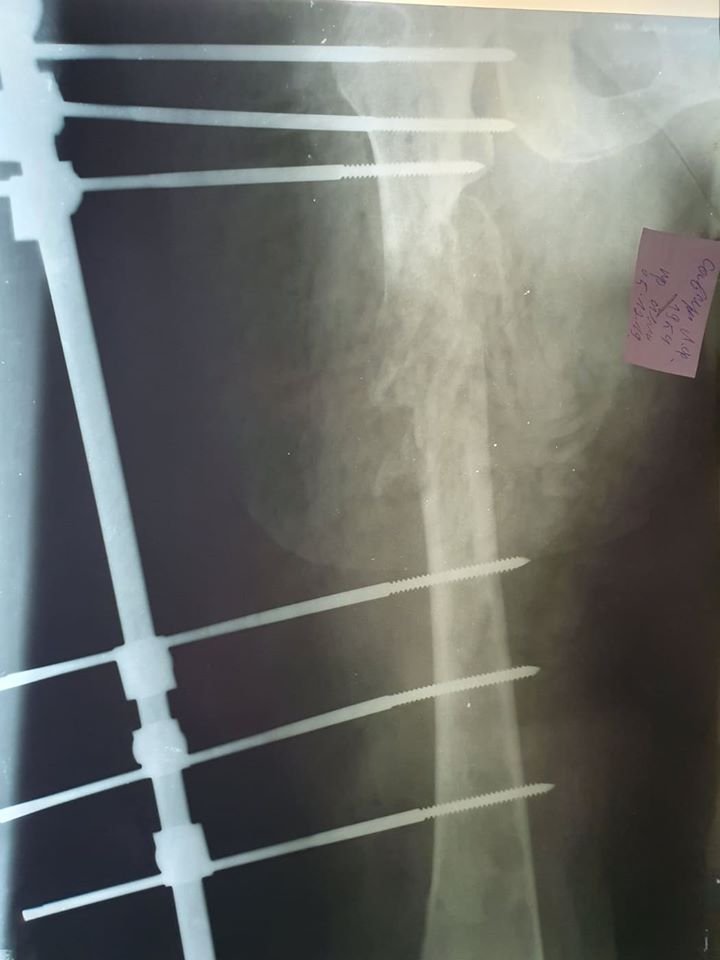

«В нас був один вихід: оскільки пластину вставити у стегно на зламі кістки було неможливо (цей метод фіксації був протипоказаний), довелося ставити апарат зовнішньої фіксації. Операцію проводили малоінвазивно, що вдалося уникнути крововтрати. Загалом такі операції мають проводитись за допомогою ортопедичного стола та спеціальної рентгенівської установки – ЕОП (електронно-оптичний перетворювач), яка дає рентгеноскопію в реальному часі, яка робиться безпосередньо в операційній з виведенням зображення на екран. Замість цього користувалися стаціонарним рентгенапаратом, який спеціально привезли в операційну. Це дало можливість двічі зробити знімок під час операції», - розповідає лікар ортопед-травматолог Андрій Бондаренко.

Тривала операція півтори години, під час якої лікарі вправили місце перелому та зафіксували його за допомогою апарату зовнішньої фіксації (зовнішніми металевими штирями).